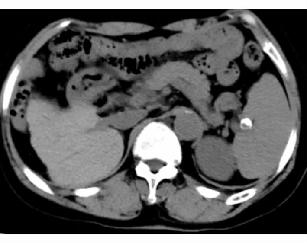

先来看一个病例:68岁女性患者,1年半前因乏力及双下肢水肿,就诊于当地医院诊断为“肝硬化”,2周前因上述症状加重。全身皮肤黏膜及巩膜轻度黄染,双手及颜面部黑色素沉着,双下肢轻度凹陷性水肿。腹部CT平扫如下图:

但患者真的是“肝硬化”吗?患者又做了磁共振检查(MRI):

最后真相大白,该患者为继发性含铁血黄素沉着症。过多的含铁血黄色在肝脏沉积,导致肝脏继发的表面不光整,造成“肝硬化”的假象。我们再仔细看肝脏CT图像,肝脏密度升高,明显高于同层面脾脏、腹主动脉管腔密度。